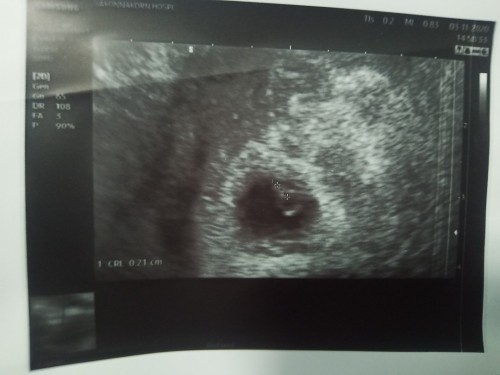

ค่ะ ตอนนี้ไม่รู้ว่าหนูน้อยเพศอะไร แต่ก็จะติดตามคุณแม่ศิวพรรอดูว่าเราจะได้ลูกเพศอะไรกันนะคะ